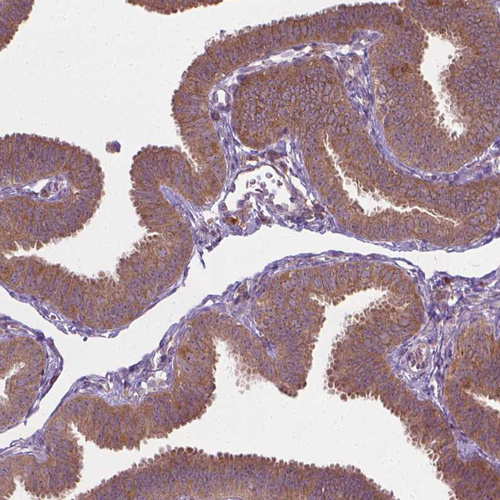

Immunohistochemical staining of human thyroid gland shows moderate cytoplasmic positivity in glandular cells.